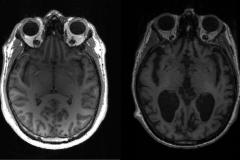

صحة التهيؤ الجيني عند الشباب يمكن أن يسبب ألزهايمر ازدادت نسبة التراجع الذهني في العامين الأخيرين منذ بدء كورونا